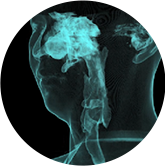

氣道

氣道三維影像重建